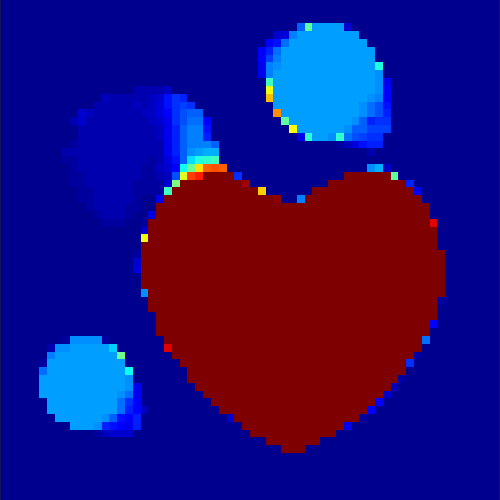

In a first test, every image sequence was reconstructed out of the exact given sinograms. Additionally we tested noise corrupted data by first scaling the sinogram by a parameter , corrupting them with Poisson noise via the MATLAB imaging toolbox command imnoise and finally rescaling the image to the original range (see figure 4). The average count number per time step (i.e. the average of the discrete -norm of the data at each time step) is approximately in case of the heart-shaped data set and ca. in case of the rat liver simulation. The results at a certain number of time steps can be seen in figure 6 and 7. For comparison, we additionally performed a reconstruction with a simple alternating EM method, keeping the assumption that the tracer can be modelled as a sum of indicator functions and subconcentration curves, but neglecting any regularization terms. In all tests, the outer iteration number was set to 1000 with 10000 inner iterations per subproblem, to obtain a result within a reasonable time period. As stopping criterion, we chose the primal dual residual (cp. [12]) for the inner and the maximum over the Frobenius norms of and for the outer iterations. The results are displayed in 6 and 7 respectively.

As one can see in both figures, the reconstruction method applied to each data set performs very well, especially in contrast to the simple alternating EM method. This clearly shows the benefits of the proposed regularization methods. In case of noise-free given data, the shape of every object, where especially the heart is of higher interest, is clearly defined. As expected, we often observe errors in the edges of each region and where two regions are directly connected (the heart and the upper left circle). This causes the algorithm to incorrectly assign these pixels to another region. Furthermore, the reconstruction difficulties increase with an increase in noise. Some more pixels are assigned to the wrong region, which leads to a small hole-like structure within the heart region and causes a slight blurring effect. In the second data set the method clearly outperforms several other approaches by providing very clearly defined regions and even reconstructing fine structures of the phantom. However, as mentioned before, a clear reconstruction of the rat liver required highly optimized parameter sets, which makes the whole problem quite susceptible to parameter changes.

Based on the sinogram data we applied the proposed algorithm in order to reconstruct the original image sequence. The results for both test cases are shown in figure 10.

As one can see, the method is able to reconstruct the regions properly, even in case of a low count number. Within a number of iterations (average of 100 outer and 10000 inner iterations), the algorithm presents a reasonable reconstruction of the region of interest and the corresponding regional tracer concentration curves. Here, the parameters were not optimized as in the case of the synthesized data sets in the previous section, but kept fixed as , and . With futher optimized parameter values one could possibly provide even better results.